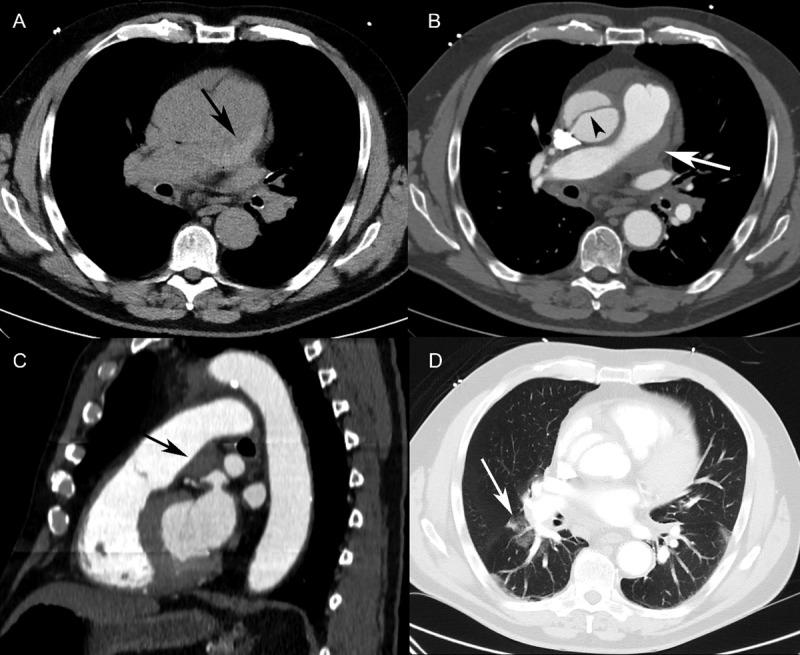

Diagnosing acute ascending aortic dissection in patients with equivocal radiologic data may rely on associated findings such as pulmonary artery intramural hematoma. The immediate diagnosis of aortic dissection is paramount in its management. Its diagnosis may be challenging on computed tomography when the intimal flap, pathognomonic of dissection, is not readily visualized. Pulmonary artery intramural hematoma may arise from rupture of the posterior wall of the ascending aorta into the common aortopulmonary adventitia as a result of acute dissection. The clinical significance of pulmonary artery hematoma is unknown, but its presence may facilitate the diagnosis of acute dissection when other radiologic findings are equivocal. Herein, we present four cases of pulmonary artery intramural hematoma associated with Stanford type A acute aortic dissection, among whom patient outcomes depended mainly on the prompt treatment the dissection.

对于影像学数据不明确的患者,诊断急性升主动脉夹层可能依赖于相关表现,如肺动脉壁内血肿。主动脉夹层的及时诊断对其治疗至关重要。当内膜瓣(夹层的特征性表现)在计算机断层扫描中不易显影时,其诊断可能具有挑战性。急性夹层时,升主动脉后壁破裂进入主动脉肺共同外膜可导致肺动脉壁内血肿。肺动脉血肿的临床意义尚不清楚,但其存在可能有助于在其他影像学表现不明确时诊断急性夹层。在此,我们报告4例与A型斯坦福急性主动脉夹层相关的肺动脉壁内血肿病例,其中患者的预后主要取决于夹层的及时治疗。